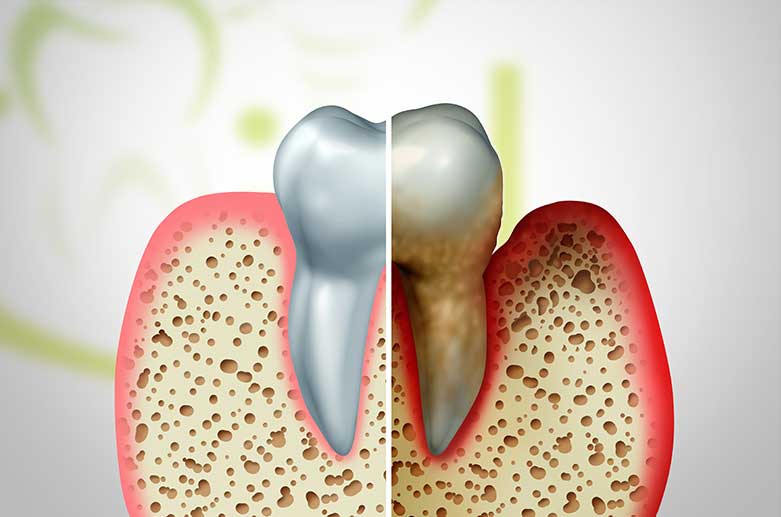

Parodontologische Behandlungen umfassen Probleme und Erkrankungen des Zahnfleischs (Zahnfleischbluten und -rötungen, Schwellungen, Zahnfleischrückgang), der Wurzelelemente und der Kieferknochen (Knochenrückgang bis hin zu Zahnlockerung und Zahnverlust).

Auch Mundgeruch kann Anzeichen einer akuten Parodontitis sein. Durch angepasste Therapieansätze und einer allgemeinen Verbesserung der Mundhygiene können wir diese Symptomatiken gezielt und erfolgreich behandeln.